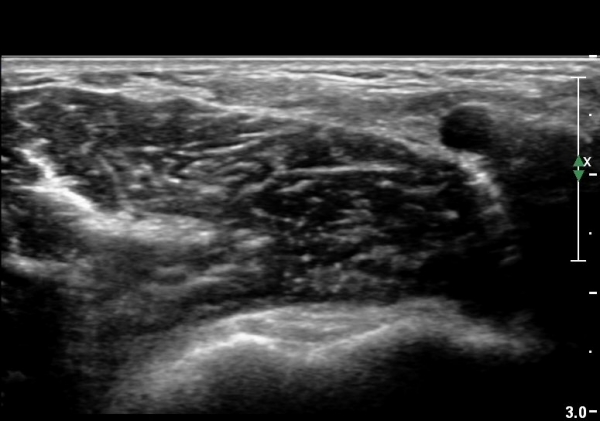

Á¶±Ý ´õ ¸»´ÜÀ¸·Î À̵¿ÇÏ¿© °üÂûÇÏ´Ï ÀÌµÎ¹Ú±Ù°Ç ½ÇÁú³» ÆÄ¿­°ú °üÀý ÁÖÀ§ ¼ö¾×Àú·ù°¡ °üÂûµÊ(±×¸² 4, 5).